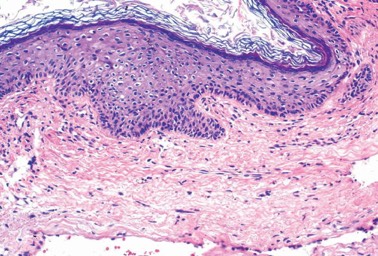

1065. На микрофотографии показана опухоль, локализующаяся в среднем ухе 48-летней пациентки, диагноз